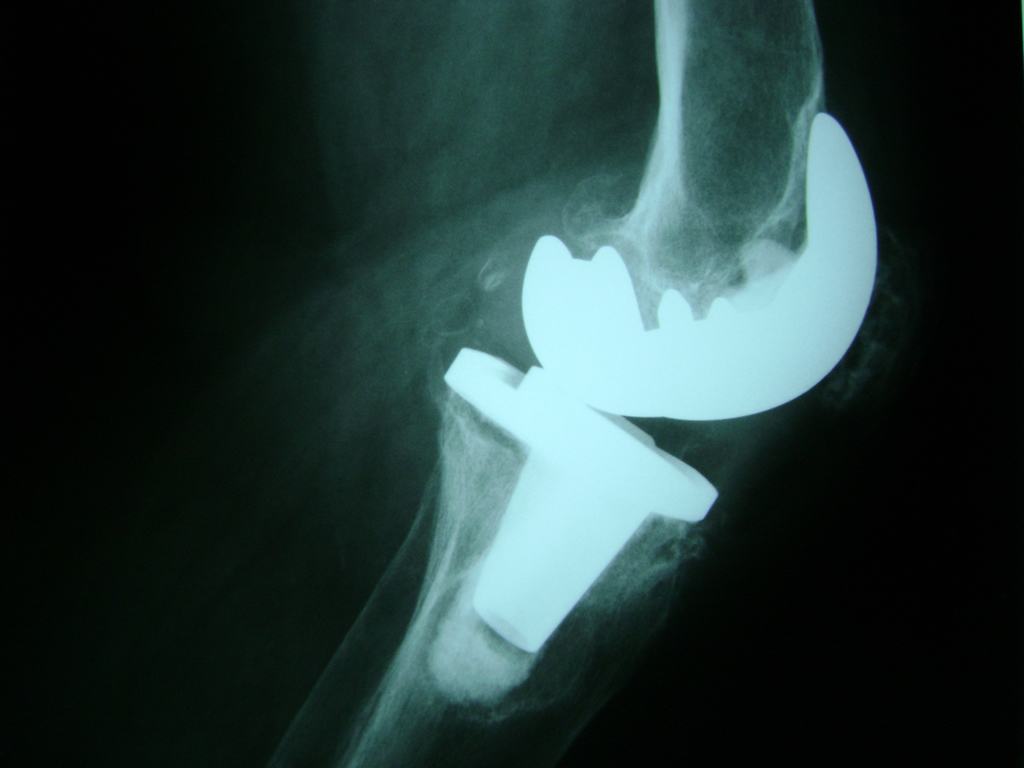

Cirugías de Rodillas

La artroscopia de rodilla es un cirugía en el cual la estructura interna de la articulación es examinada ya sea para realizar un diagnostico o para realizar un tratamiento, este procedimiento se realiza utilizando un instrumento parecido a un pequeño tubo llamado artroscopio.